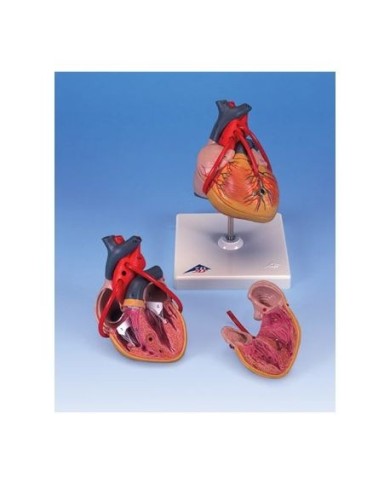

Fra i modelli di base segnaliamo il modello di cuore classico in due parti, in cui le due metà del cuore sono tenute insieme da potenti magneti.

Inoltre nella categoria sono presenti anche i modellini anatomici di cuore con bypass e con sistema di conduzione, fino ai modelli anatomici comparativi di patologie del cuore.